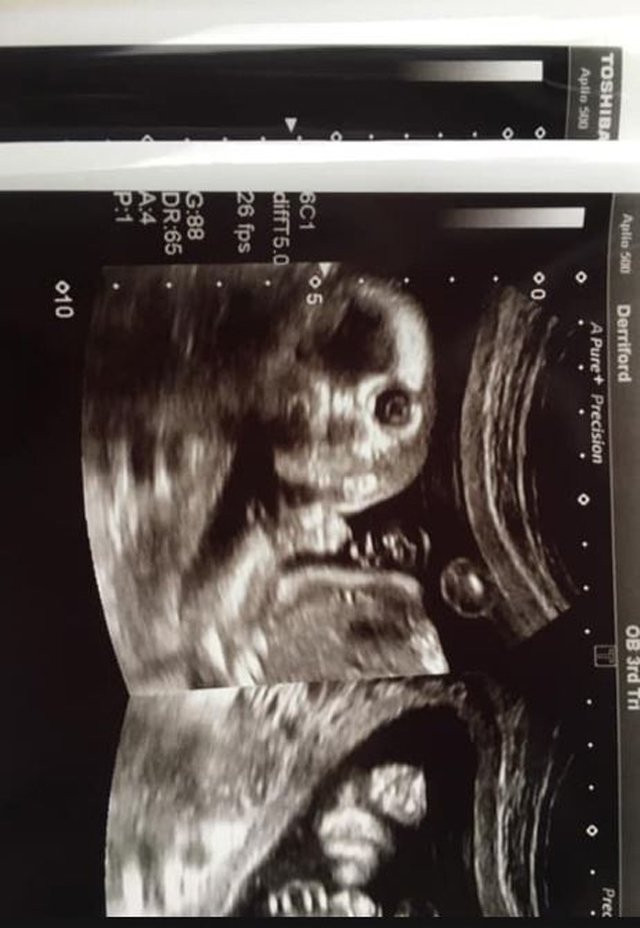

Việc siêu âm sẽ giúp cô Jo Greer kiểm tra được tổng thể sức khỏe của thai nhi trong bụng, bao gồm tình hình của não, tim, tủy sống, thận và bụng. Tuy nhiên trong lần siêu âm ở tuần thứ 20 này, Jo Greer đã phát hiện ra một điều vô cùng bất ngờ và thú vị. Ảnh quét siêu âm cho thấy em bé của chị Jo Greer đang nhìn thẳng vào phía máy ảnh. Đây là điều rất hiếm xảy ra bởi các em bé thường trốn tránh máy ảnh.

Bức ảnh siêu âm cho thấy thai nhi nhìn thẳng vào máy quét.

Chị Jo Greer chia sẻ: "Tất cả các hình ảnh siêu âm đều vô cùng dễ thương và ổn định, tuy nhiên khi nhìn thấy bức ảnh này, tôi và bác sĩ đã hết sức kinh ngạc. Chúng tôi gần như không thể ngừng cười. Nữ hộ sinh của tôi nói rằng đây là điều không thường xuyên xảy ra. Con tôi đã nhìn thẳng vào máy ảnh một cách chằm chằm". Không chỉ chị Jo Greer, ngay cả bác sĩ siêu âm và nữ hộ sinh cũng cảm thấy kinh ngạc trước hình ảnh này.

Tất nhiên, chị Jo Greer và bác sĩ cũng có những hình ảnh siêu âm thai nhi ở nhiều góc độ khác, không chỉ góc thẳng mặt mà còn cả góc nghiêng để đánh giá tình hình sức khỏe một cách chính xác nhất. Tuy nhiên, hình ảnh trên vẫn gây ấn tượng sâu đậm nhất với họ. Ngoài ra, bác sĩ cũng cho biết thai nhi của chị Jo Greer hoàn toàn khỏe mạnh, không phát hiện bất cứ điều bất thường nào.